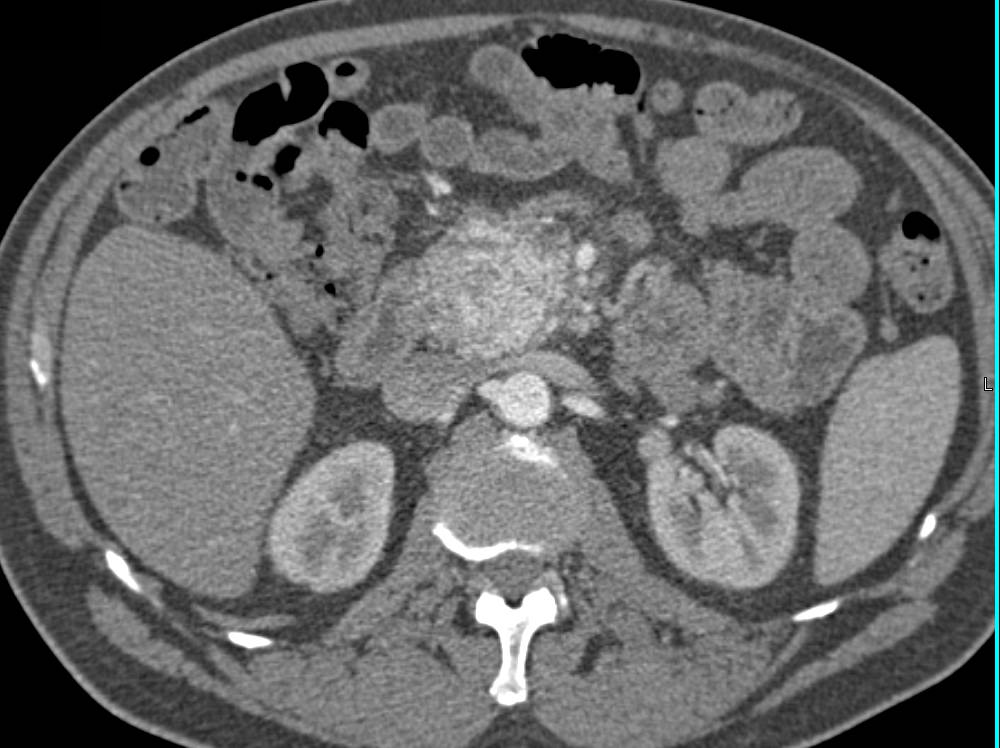

Pancreatic Cancer with Arterial and Venous Invasion and Liver Metastases